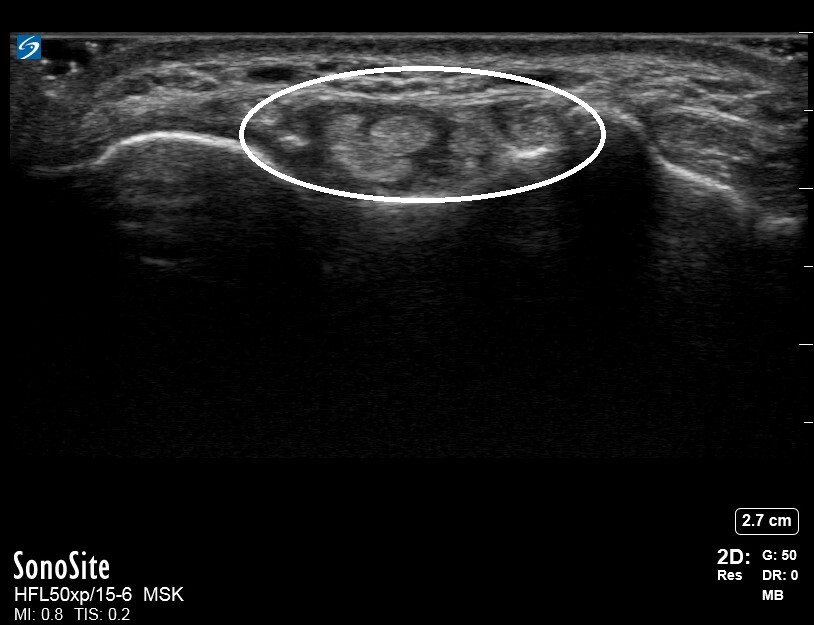

Wrist Compartment Four Image